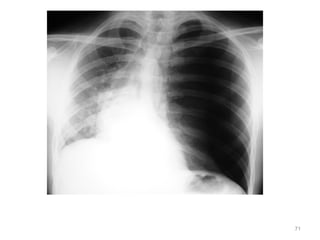

71

• 66.

 Primary Survey –Awake, alert, talking to provider – Breathing • RR = 27 • O2 sat = 93% • Absent breath sounds on left – What do you want to do next? 66

• 67.

Needle decompression: Rushof air heard consistent with pneumothorax 67

• 68.

Exam – Awake, diaphoretic –Pulse = 120, weak – BP = 90/60 What do you want to do next? 68

• 69.

 Chest tubeplaced – Rush of air heard consistent with pneumothorax  Repeat Vital Signs – Pulse 98 – BP 120/76 – RR = 15 – O2 sat = 99% NRBM  What do you want to do next? 69

• 70.

– Circulation – Disability –Exposure • Secondary survey 70